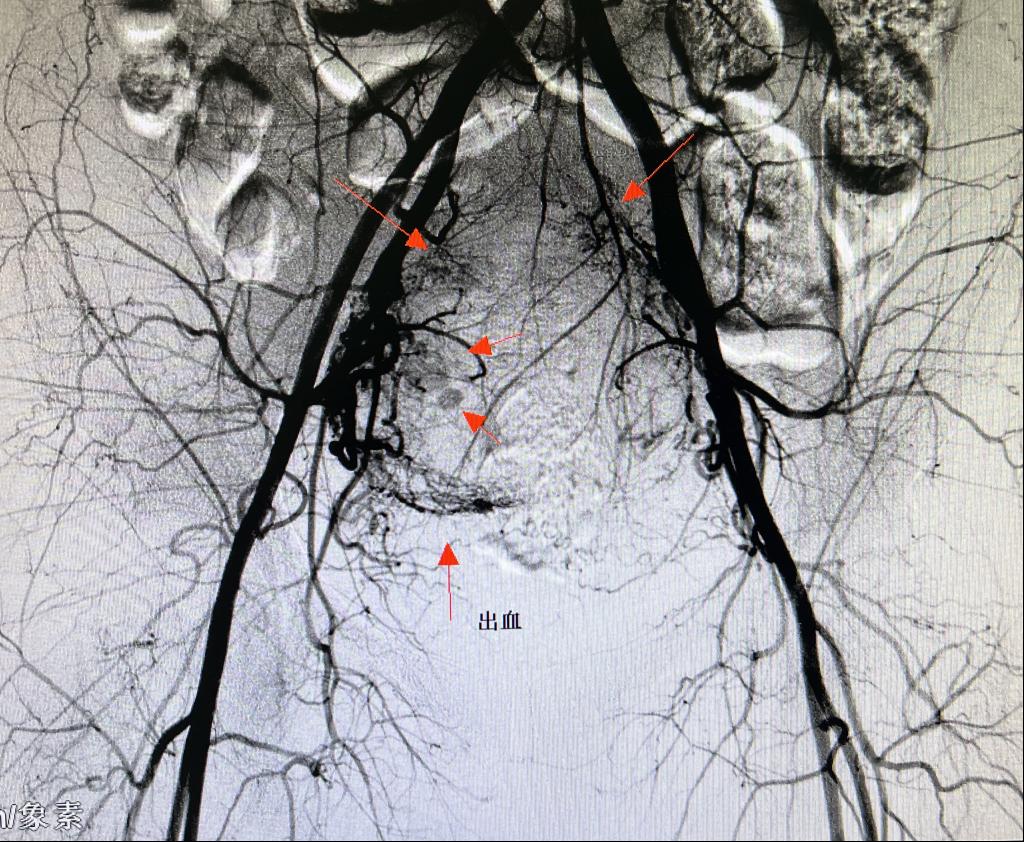

患者王某,女性,38岁,瘢痕妊娠二月余药流+清宫术后大出血,出血量2000ml以上。正值晚21时,各术室满台,主治医师谢纱将急会诊情况上报给主任后,科室同事积极配合,立即开通DSA第二夜间绿色通道进行危急重患者介入手术。

为有效避免介入术后患者截石位清宫导致股动脉穿刺口血肿或假性动脉瘤的发生,患者平卧24小时绝对制动,选择经肱动脉(右上肢)穿刺,术中患者休克血压(80/55mmHg),又增加了穿刺难度。谢纱精准穿刺右肱动脉成功,经盆腔血管造影后明确子宫出血动脉即行超选择栓塞。术闭出血立止、术后生命体征平稳。